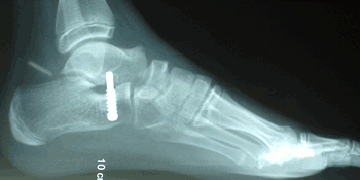

RESULTADOS

Caso 1: Pie plano esencial laxo